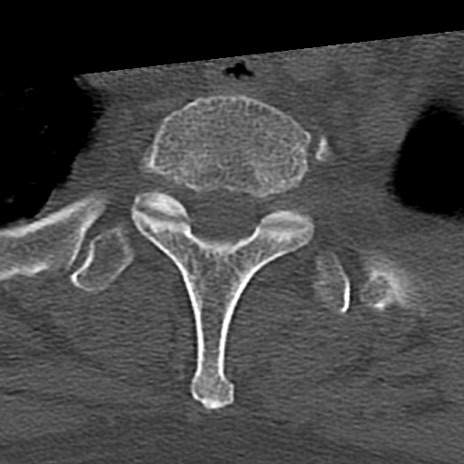

頚椎CT

横断像